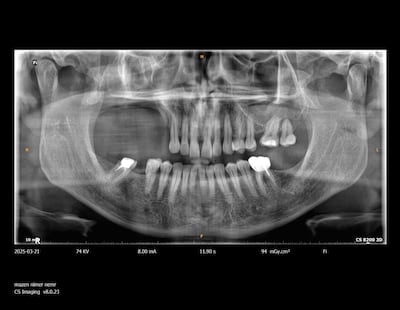

Nimer Altaher, from Jordan, was diagnosed with ameloblastoma, a rare but benign tumour of the upper jaw, in 2022. While usually non-cancerous, the tumour begins to grow in cells that form tooth enamel, and typically expands in the jawbone close to the molar teeth.

Doctors at Medcare Dentofaces in Dubai suggested a removable maxillofacial prosthesis as a viable option, as a 3D-printed device custom-made for Mr Altaher would fit perfectly inside what was left of his existing jaw.

Specialist scanners created a digital image of his mouth and then used that information with a 3D printer to create an artificial jaw that would fit perfectly inside his mouth. He has been using the fitting since August.

They used advanced digital imaging, precision 3D modelling, and custom casting technologies to craft and fit the removable partial denture.